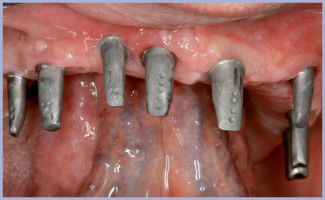

- Figg. 2, 3 – Impianti inseriti nel mascellare superiore

- Fig. 3

Arcata inferiore: posizionamento di 8 impianti Exacone™ e riabilitazione con protesi fissa su impianti.